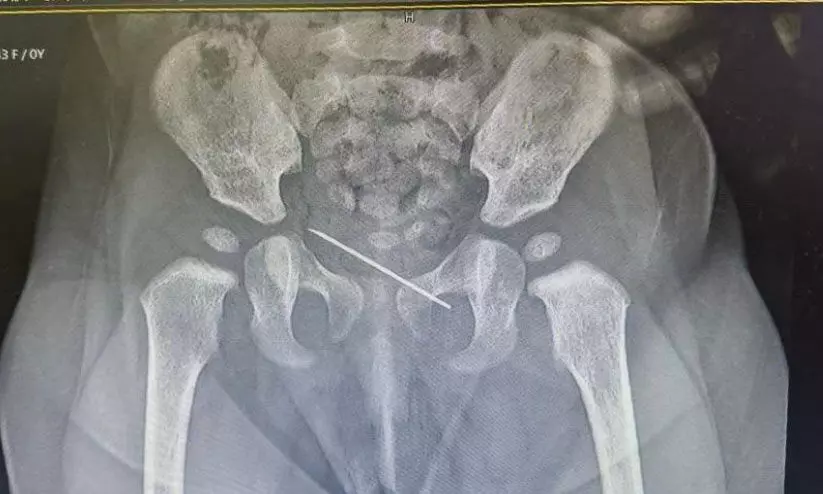

text_fieldsമനാമ: സാധ്യമായ ഏറ്റവും മികച്ച ചികിൽസ രോഗികൾക്ക് ലഭ്യമാക്കുന്ന അൽ ഹിലാൽ ഹെൽത്ത് കെയർ ഗ്രൂപ്പ് ആരോഗ്യ പരിചരണ രംഗത്ത് വീണ്ടും ശ്രദ്ധേയമാകുന്നു. നാഭിയിൽ ചർമ്മത്തിന് താഴെ അസാധാരണമായ വസ്തു ഉള്ളതായി അനുഭവപ്പെട്ട ഏഴ് മാസം പ്രായമുള്ള പെൺകുഞ്ഞിനെ രക്ഷപ്പെടുത്തിയതാണ് ഏറ്റവും പുതിയ സംഭവം. മുഹറഖിലെ അൽ ഹിലാൽ ആശുപത്രിയിലെ സ്പെഷ്യലിസ്റ്റ് പീഡിയാട്രീഷ്യൻ ഡോ. ഗൗതം എ. ശിവാനന്ദയെ കാണാനെത്തിയ കുട്ടിയെ പരിശോധിച്ചപ്പോൾ, ഏകദേശം 3.5 സെൻറീമീറ്റർ നീളത്തിലുള്ള പൊട്ടിയ സിറിഞ്ച് സൂചിയാണ് ആശുപത്രിയിലെ സംഘം കണ്ടെത്തിയത്.

ഡോ. പി.യു മുഹമ്മദ് സലീമിന്റെ സഹായത്തോടെയാണ് ലോക്കൽ അനസ്തേഷ്യയിൽ സൂചി വിജയകരമായി നീക്കം ചെയ്തത്. വിജയകരമായ ശസ്ത്രക്രിയയ്ക്ക് ശേഷം കുഞ്ഞിനെ ആശുപത്രിയിൽ നിന്ന് ഡിസ്ചാർജ് ചെയ്തതായി ആശുപത്രി വൃത്തങ്ങൾ അറിയിച്ചു. വൻകുടൽ, മലാശയ ശസ്ത്രക്രിയ, ട്രോമ ആൻഡ് ബേൺ, എൻഡോക്രൈൻ സർജറി, ബാരിയാട്രിക് സർജറി, മൾട്ടി ഡിസിപ്ലിനറി ഹെപ്പറ്റോബിലിയറി പാൻക്രിയാസ് സർജറി എന്നിവയുൾപ്പെടെ വിവിധ ഉപവിഭാഗങ്ങളിൽ സമഗ്രമായ ശസ്ത്രക്രിയാ കൺസൾട്ടേഷനും പരിചരണവും അൽ ഹിലാൽ ഹെൽത്ത്കെയർ ഗ്രൂപ്പ് നൽകുന്നുണ്ട്. അൽ ഹിലാലിലെ വിദഗ്ധ ശസ്ത്രക്രിയാ വിദഗ്ധർ വിവിധ സ്പെഷ്യാലിറ്റികളിൽ ഫെലോഷിപ്പ്-പരിശീലനം നേടിയവരും അതത് വിഭാഗങ്ങളിലെ പ്രശസ്തരുമാണ്.